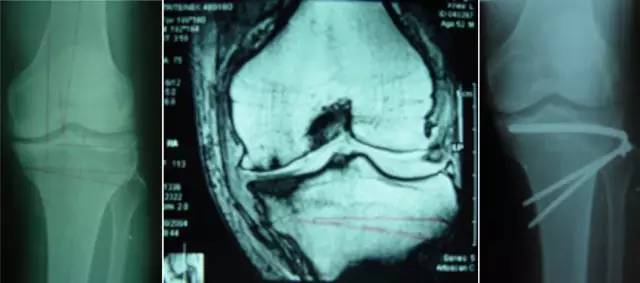

开展关节镜下交叉韧带单、双股解剖重建技术、膝关节多韧带损伤的一期修复重建术、半月板缝合技术、骨软骨移植技术、同种异体移植治疗交叉韧带损伤、双隧道重建交叉韧带、肩关节镜下肩袖修补和SLAP损伤修补术,及肘、踝、腕、髋关节镜术。专业运动员伤病诊治技术、股骨髋臼撞击综合症、股骨头坏死阶梯治疗技术、骨软骨移植技术。

膝关节镜-半月板损伤

膝关节镜-前交叉韧带重建

膝关节镜-关节内游离体